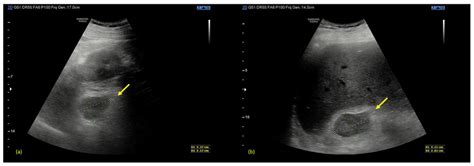

• Imaging studies, such as CT scans or MRIs, to assess the adrenal glands